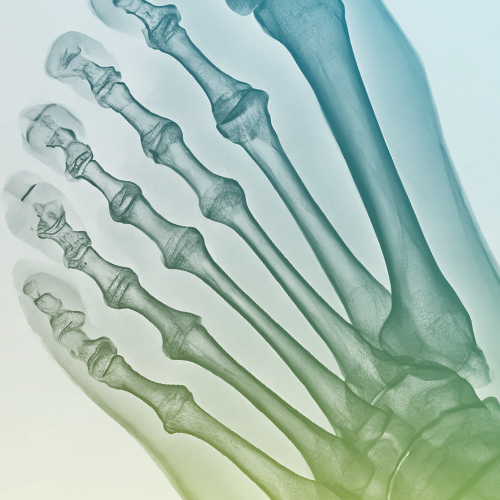

Foot Surgery

Addresses complex foot structure issues (26 bones, 33 joints). Treats deformities affecting feet and toes to maintain stability and movement for daily activities.